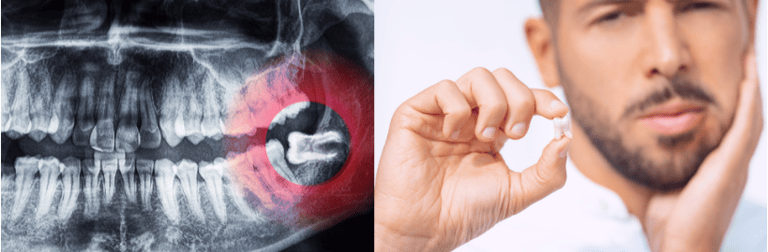

Extrações (inclusive Siso);

Radiologia Odontólogica (Panorâmica, Telerradiografia, periapical);